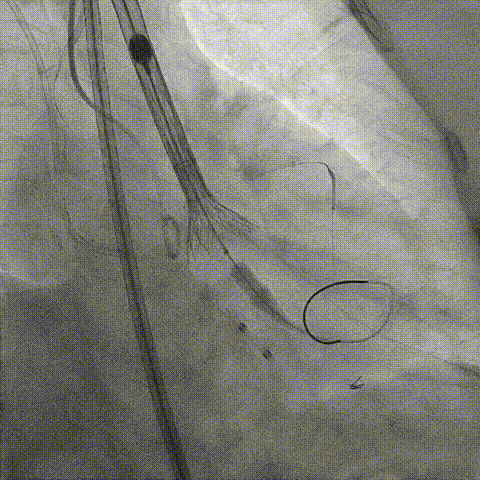

调整支架位置

释放冠脉支架

释放瓣膜

造影评估

支架内后扩张

冠脉造影

根部造影

最终结果

动脉瓣瓣周轻度反流。

经主动脉口收缩期血流最大速度约1.5m/s,最大跨瓣压差约10mmHg。